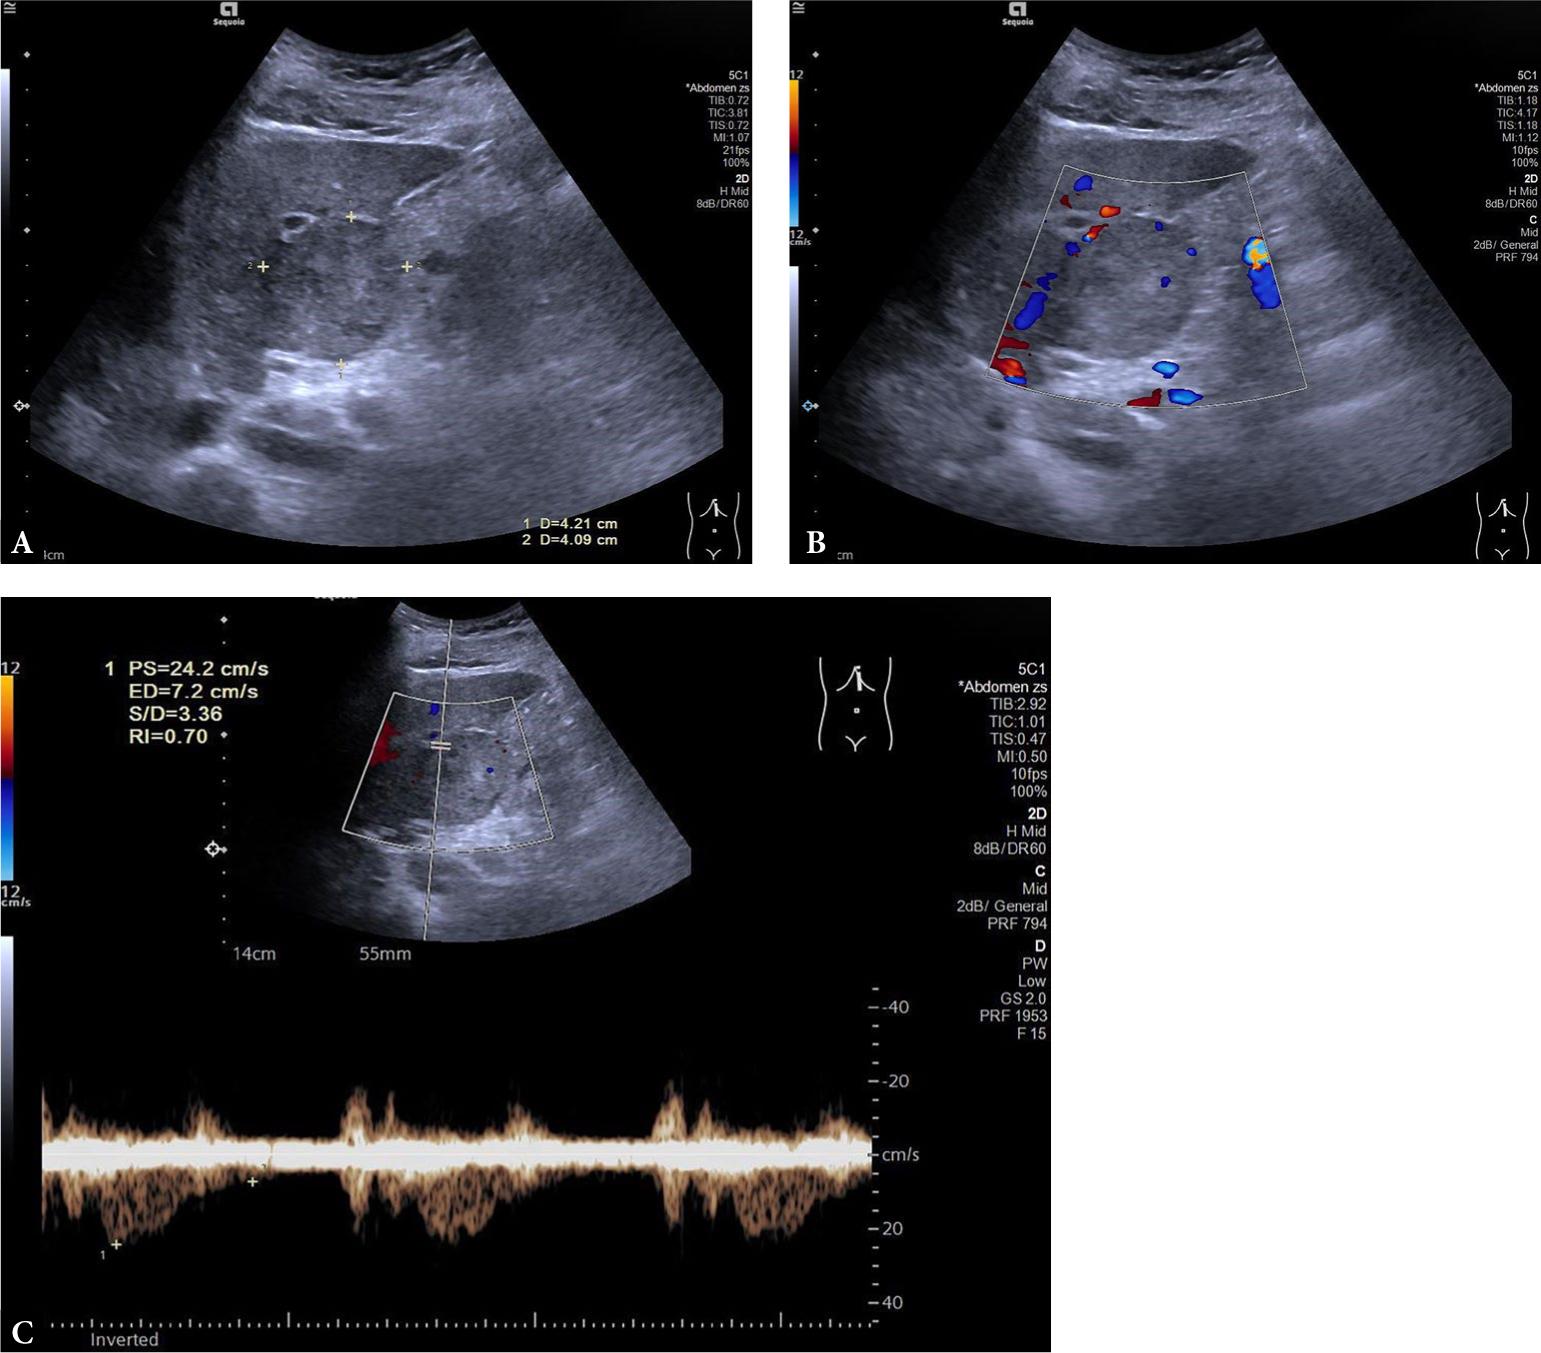

Fig. 1.